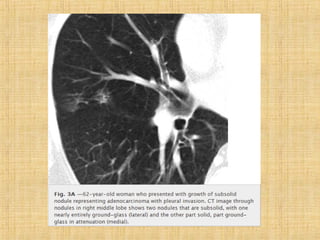

As principais informações do documento são: 1. Discute os padrões de doença pulmonar causados por metástases, incluindo nódulos, espessamento intersticial e obstrução das vias aéreas. 2. A prevalência de metástases pulmonares varia de 30-55% dependendo do tumor primário, e são mais comuns em pacientes acima de 50 anos. 3. Os achados clínicos mais comuns são dispneia, hemoptise e febre, enquanto exames de escarro ou lavado brô